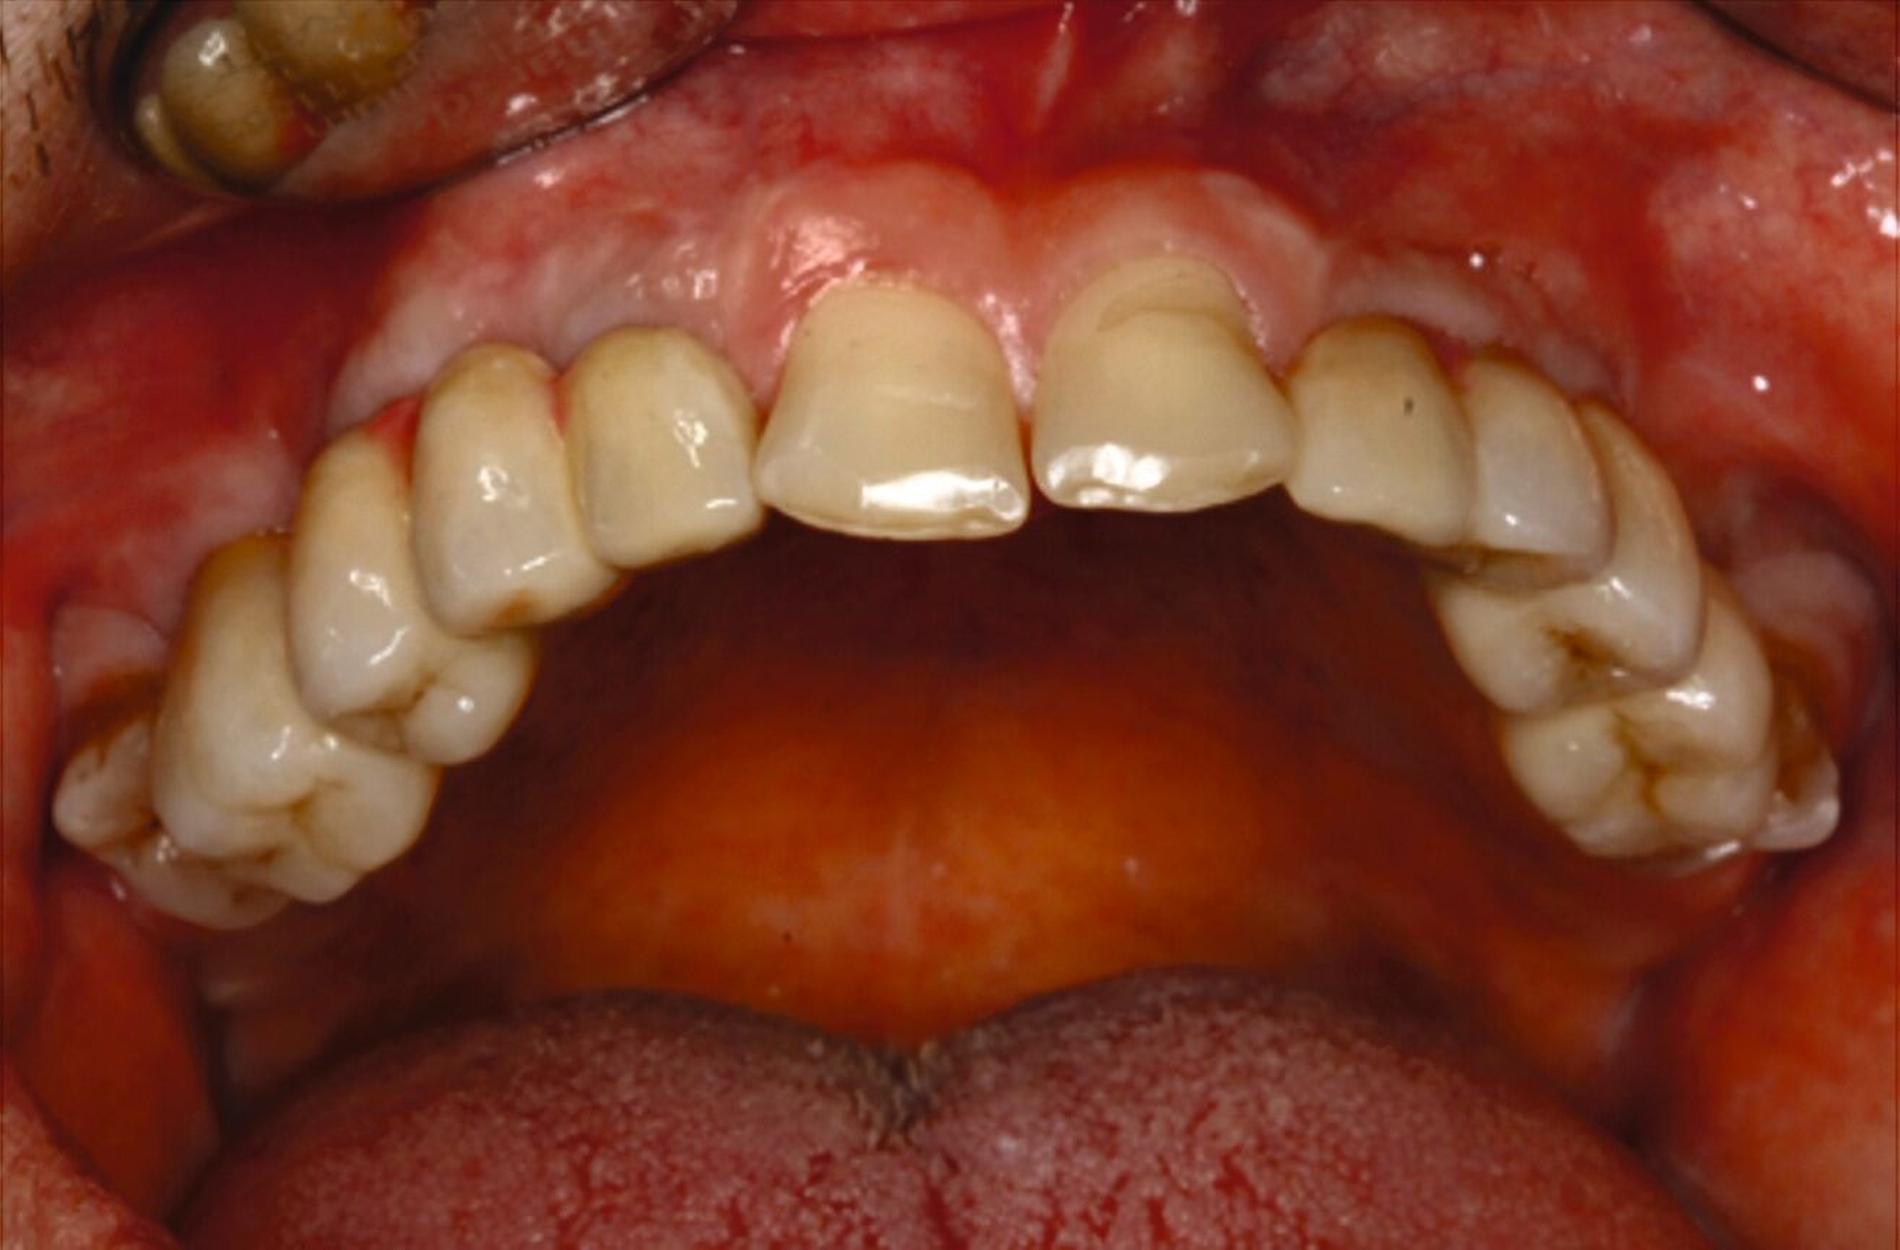

Nach komplikationsfreiem Heilungsverlauf (Abbildung 8) erfolgte die Freilegung der Implantate, die Einsetzung von Gingivaformern und die Anpassung des Interimsersatzes (Abbildung 9). Wegen der dadurch anfallenden zusätzlichen Kosten verzichtete der Patient auf ein Langzeitprovisorium.

Über Abutmenteinproben, Korrekturen der angestrebten Bisslage sowie Gerüst- und Rohbrandeinproben erfolgte die definitive Eingliederung der festsitzenden Versorgung auf den natürlichen Zähnen und den Implantaten. Zehn Monate nach Beginn des mehrzeitigen operativen Vorgehens konnte die komplexe interdisziplinäre Versorgung des Patienten der äußerst ungünstigen Zahn- und Bisssituation nahezu abgeschlossen und zur Zufriedenheit des Patienten finalisiert werden (Abbildung 10).